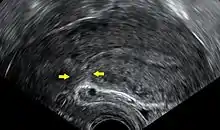

Transvaginal ultrasonography of a uterus years after a caesarean section, showing the characteristic scar formation in its anterior part

A caesarean section is associated with risks of postoperative adhesions, incisional hernias (which may require surgical correction), and wound infections.[17] If a caesarean is performed in an emergency, the risk of the surgery may be increased due to a number of factors. The patient's stomach may not be empty, increasing the risk of anaesthesia.[18] Other risks include severe blood loss (which may require a blood transfusion) and postdural-puncture spinal headaches.[17]